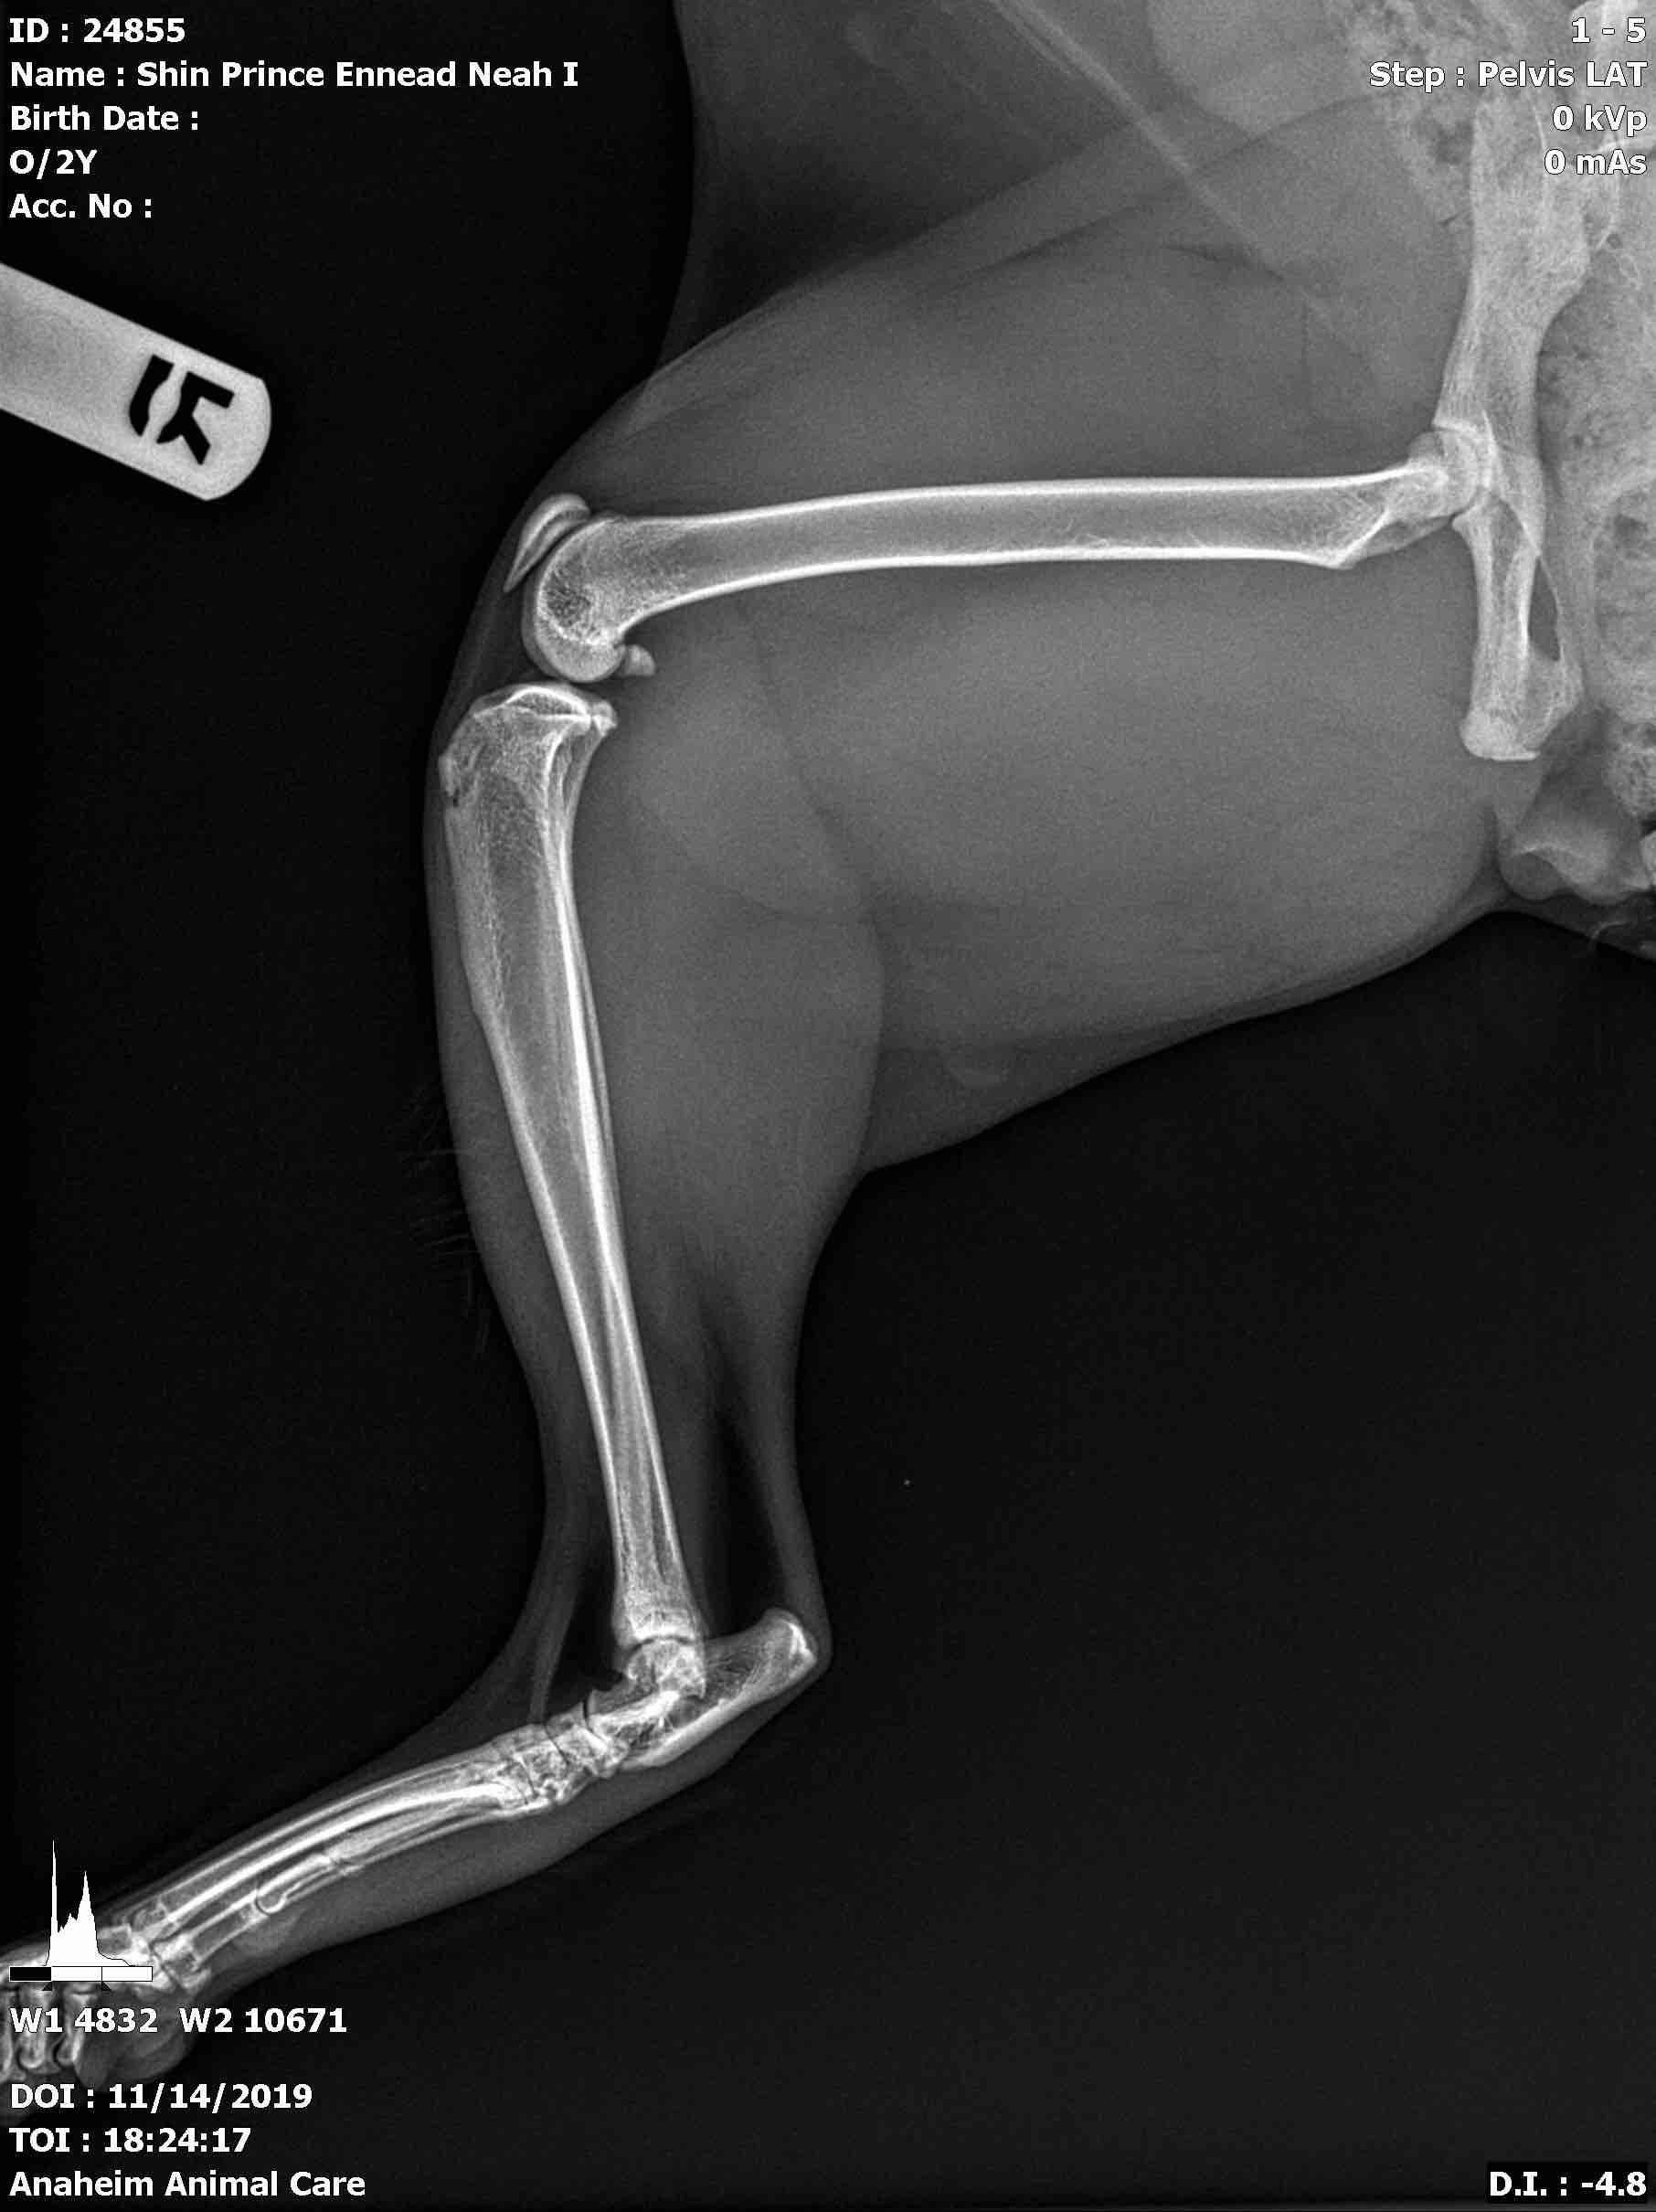

Pet's info: Cat | Savannah Cat | Male | neutered | 2 years and 5 months old | 18 lbs

Other doctor commented nothing seemed wrong. But if those tiny pieces are bone splinter, he would have to do surgery, right...? How much does if usually range? He is eating/drinking good, walking/jumping/running -though I asked him not to. But after taking meds given by doctor, he seems having constipation. Unsure but foul odor is coming out from his bottom hole.

I'm not really seeing bone splinters on the knee/circled area. If you mean the free moving bone, that is the knee-cap and is a normal finding. There could be a tiny bit of debris in the joint capsule surrounding, but it is hard to tell. It would be best to have Neah evaluated by an orthopedic surgeon to determine if surgery is needed. They can also provide you with cost estimates depending on what care is needed as prices will vary by individual clinic. Some medications can cause changes to bowel habits. If Naeh seems in a lot of distress or very uncomfortable, I would let your vet know in case they need to add in a laxative or change medications to help.